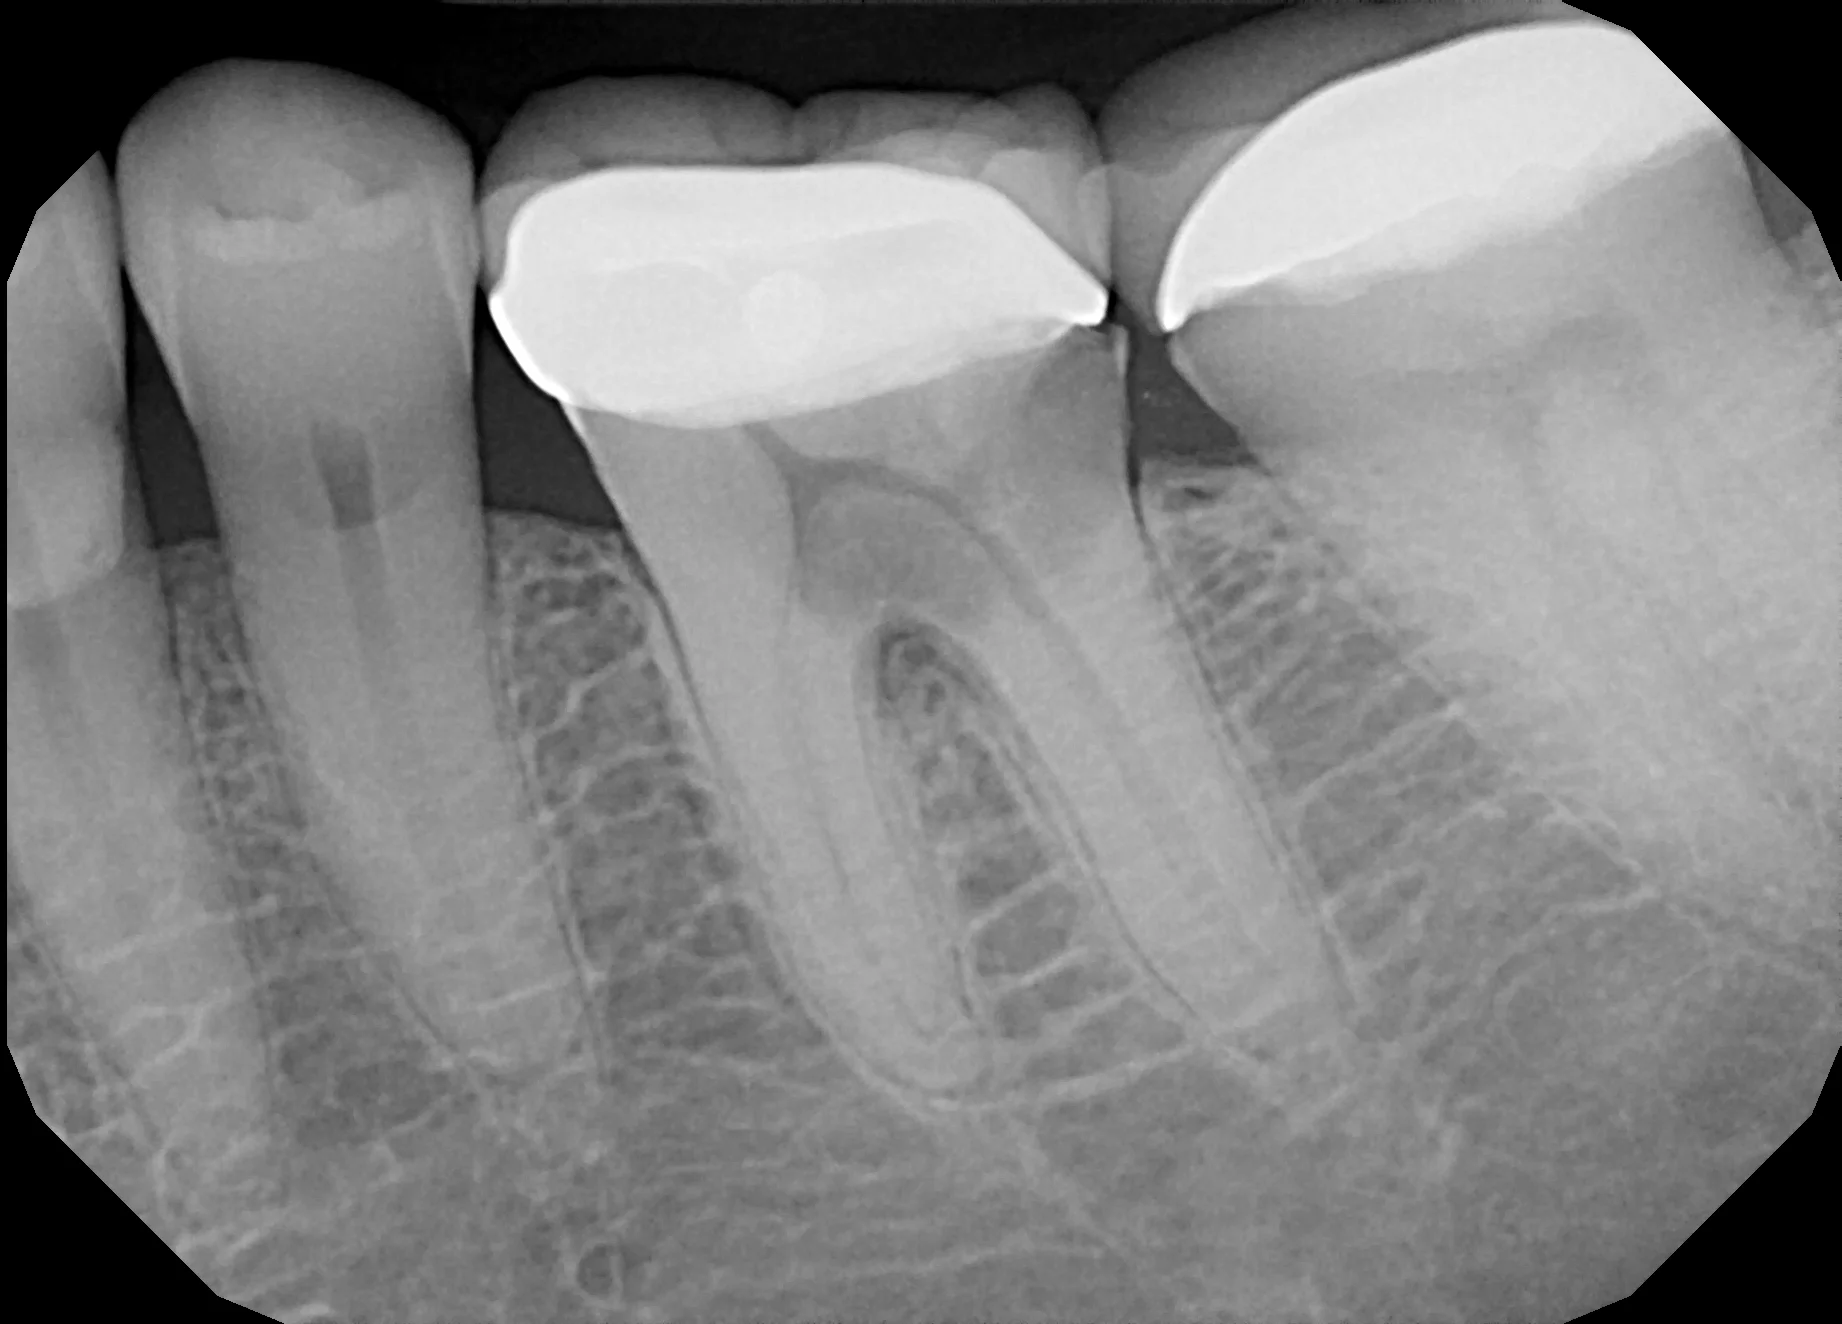

Use the form below to submit your information and our team will provide a second opinion on your dental xray. If you don't have access to the original file, then a photo of your xray will work too.